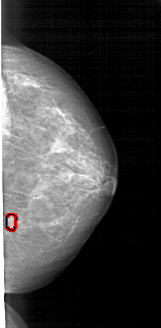

A_1715_1.LEFT_MLO

LEFT_MLO LINES 5491 PIXELS_PER_LINE 2536 BITS_PER_PIXEL 12 RESOLUTION 43.5 NON_OVERLAY

FILE: A_1715_1.RIGHT_MLO.OVERLAY

TOTAL_ABNORMALITIES 1

ABNORMALITY 1

LESION_TYPE MASS SHAPE LOBULATED MARGINS OBSCURED

ASSESSMENT 3

SUBTLETY 3

PATHOLOGY BENIGN

TOTAL_OUTLINES 1

BOUNDARY